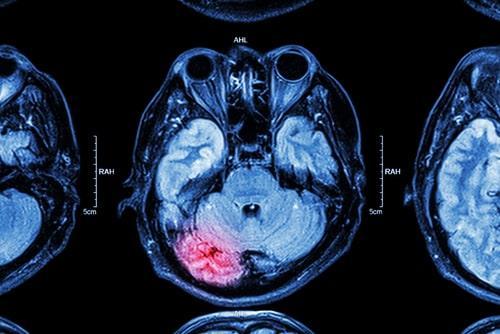

March is National Brain Injury Awareness Month. It is important to recognize the common causes of brain injuries in an effort to treat and prevent these types of injuries from occurring in the first place. Although hitting your head can happen anywhere, there are certain factors that may increase the likelihood of this happening. For example, reckless driving can cause vehicle collisions or pedestrian accidents that result in severe head trauma. A traumatic brain injury (TBI) typically is caused by a sudden or violent blow or jolt to the head or neck. Mild traumatic brain injury can impact brain cells temporarily. More serious traumatic brain injury can result in bruising, bleeding, and tissue damage to the brain. These injuries can lead to long-term complications and even death.

Even though a person may not immediately feel or notice symptoms of a brain injury, it is crucial that they seek medical attention as soon as possible after being involved in an accident. In some cases, the signs may be subtle and internal, but they can get worse over time. Brain swelling or bleeding can require surgery to repair and can be life-threatening without prompt care.